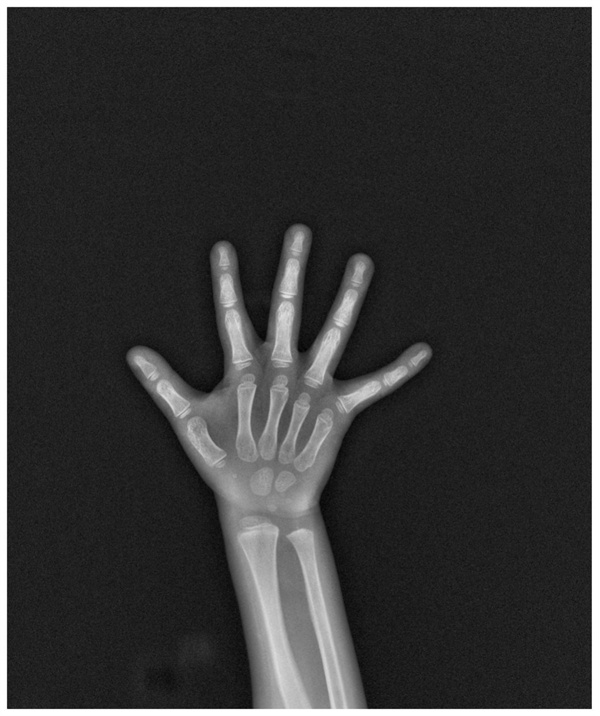

Human growth and development can be represented by two “ages”, namely life age (calendar age) and biological age (bone age). Bone age, short for skeletal age, is determined by specific images of bones in X-ray photography. Compared with the age we usually refer to (calendar age), bone age is of great significance for evaluating the growth and development of children and adolescents, disease diagnosis, and monitoring clinical treatment.

There are many methods for bone age determination. The most familiar one is to take an X-ray of the left wrist of a person. Doctors observe the development degree of the ossification centers at the lower ends of the phalanges, carpal bones, and radius and ulna of the left palm through the X-ray to determine the bone age.